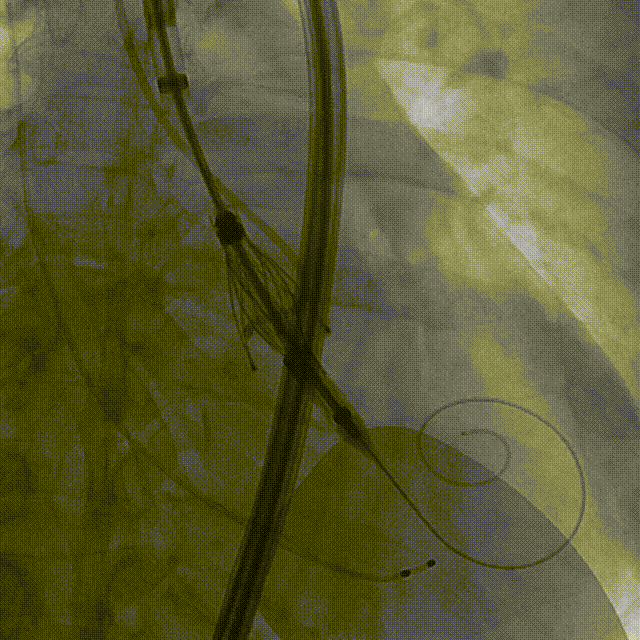

Case 3

瓣上风湿性粘连伴有狭窄重度反流

手术过程:5A 标准化流程SOP

术前右窦中心造影

大鞘植入

瓣膜调弯解离

定位键窦对齐验证

定位键入窦验证

深度检查

一键释放

后扩后造影